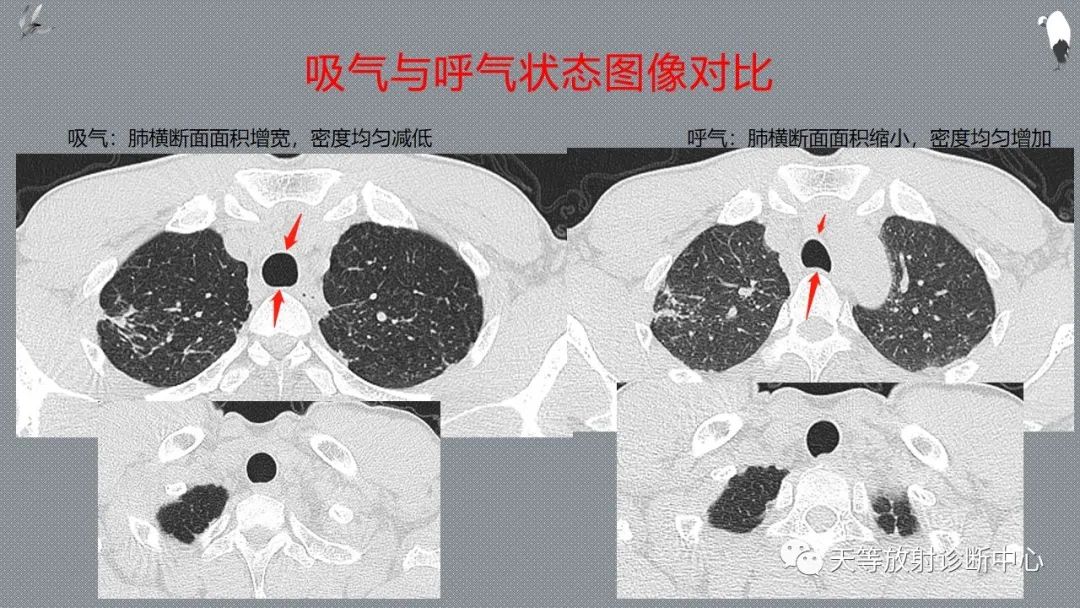

正常吸气及呼气HRCT表现—探索小叶性含气增多影像学

CT可以观察到底是吸气状态还是呼气状态的图像,这有利于对肺内气体量的评价。

充分吸气后进行CT扫描,有利于把肺内正常的含气组织和高密度的肺间质结构进行区分,利用充分显示病灶。

更有利区别局灶性肺含气不张与异常之间的对比

排除肺弥漫性或局限性气道阻塞小气道病变。